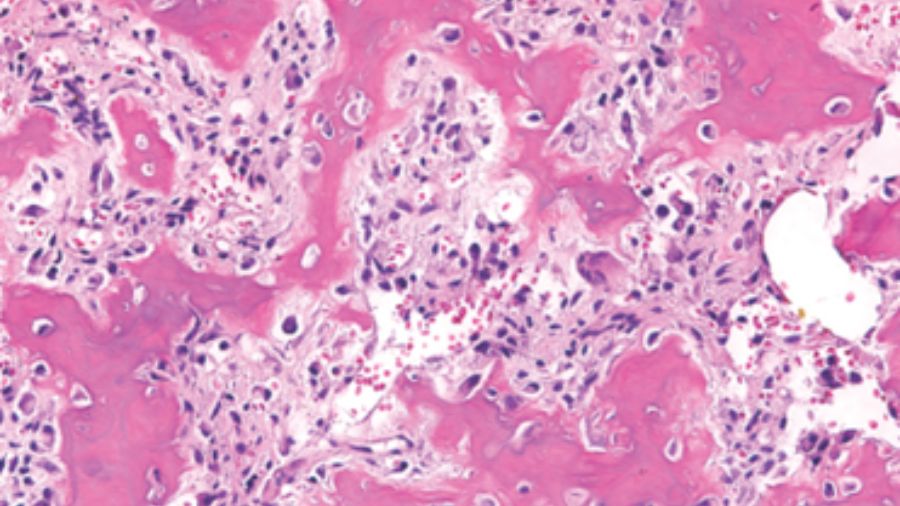

A CT-guided biopsy demonstrated it was osteoblastoma, so we did an intralesional tumor curettage, leaving a rim of bony shell in the surrounding area. The postoperative pathology confirmed it was osteoblastoma, with focal epithelioid morphology.

So, we did the second intralesional tumor excision. Histopathology revealed epithelioid osteoblasts proliferated in sheets. Postoperative CT showed the recurrent lesion was excised grossly.

This time, after the tumor arteries embolization, a more aggressive tumor excision was undertaken with sacrificing the nerve roots. The postoperative pathology showed the tumor composed of abundant epithelioid osteoblasts, but no signs of malignant appearance. The postoperative CT and MRI showed the recurrent tumor was excised grossly.

In terms of histopathology, the tumor consists of large osteoblasts producing osteoid and woven bone.

Dorfman and Weiss proposed the conception of aggressive osteoblastoma, which represented a borderline lesion between benign osteoblastoma and osteosarcoma. These tumors were likely to recur but never metastasize. They occurred in an older group, mainly in the spine, and often larger than 4cm in diameter. However, the most prominent feature is the presence of so-called epithelioid osteoblasts.

Do epithelioid osteoblasts tell us this is a wolf?